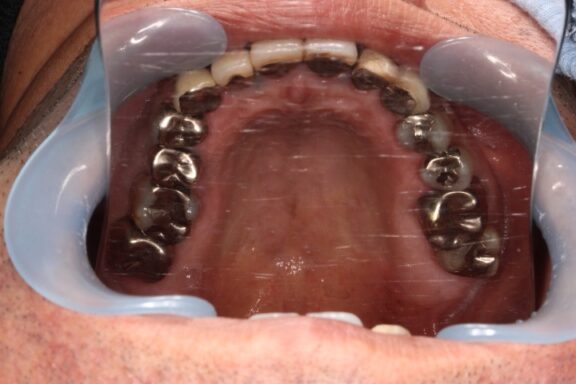

前歯には、過去に他院様にてプラスチックが前面に貼り付けてある「前装冠」という保険診療のクラウン(被せ物)が施されている状態でした。

奥歯には複数の歯に銀を主成分とするメタル修復がされている状態でした。